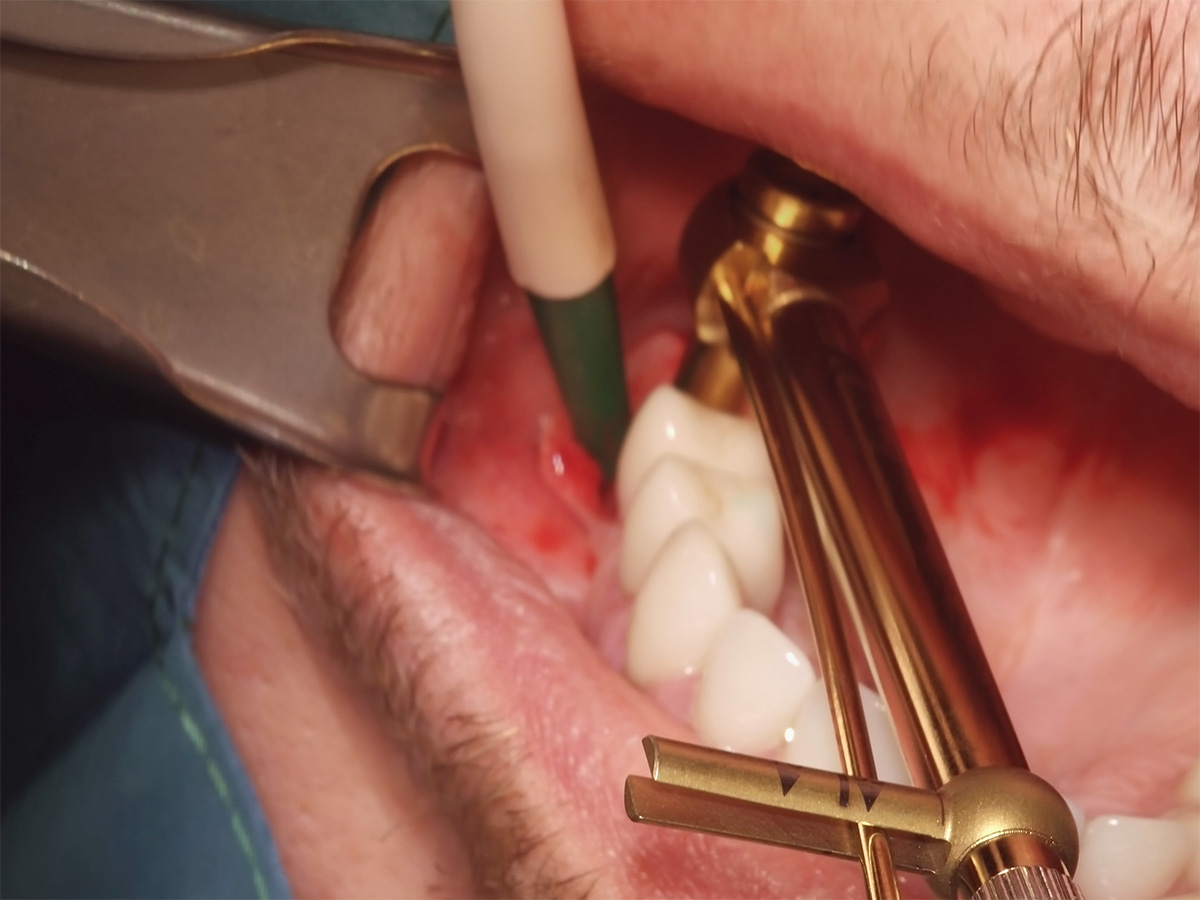

Abbildung 5

Implantatbettaufbereitung mit der Bone Condensing Methode (Versah Densah Burs).